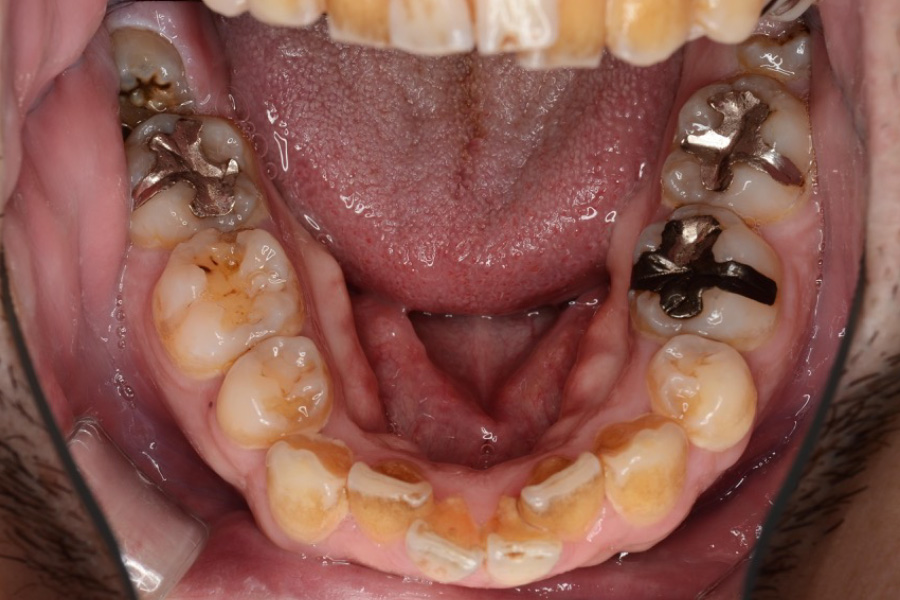

【30代男性】

下の歯のガタつきを

インビザライン矯正で治療したケース

治療前

| 主訴 | 下の歯のガタつきが気になる |

| 期間 | 1年 |

| 費用 | 220,000円〜660,000円 (デンタルローン 3,100〜6,600円/月) |

| 治療内容 | インビザライン矯正 小臼歯抜歯 |

| 治療に伴うリスク | 矯正終了後は、リテーナーを指示通りに使用し、歯の後戻りを防ぐ必要があります。 |